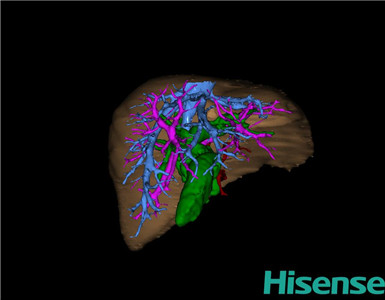

将0.625mm双源薄层CT资料的静脉期和动脉期Dicom格式文件导入海信CAS系统。

通过调节窗宽窗位调整CT序号,对肝实质,胆囊,胆总管,下腔静脉,肝动脉、门静脉及肝静脉等进行三维重建;系统自动计算肝脏体积。

术前三维重建:

重建图片